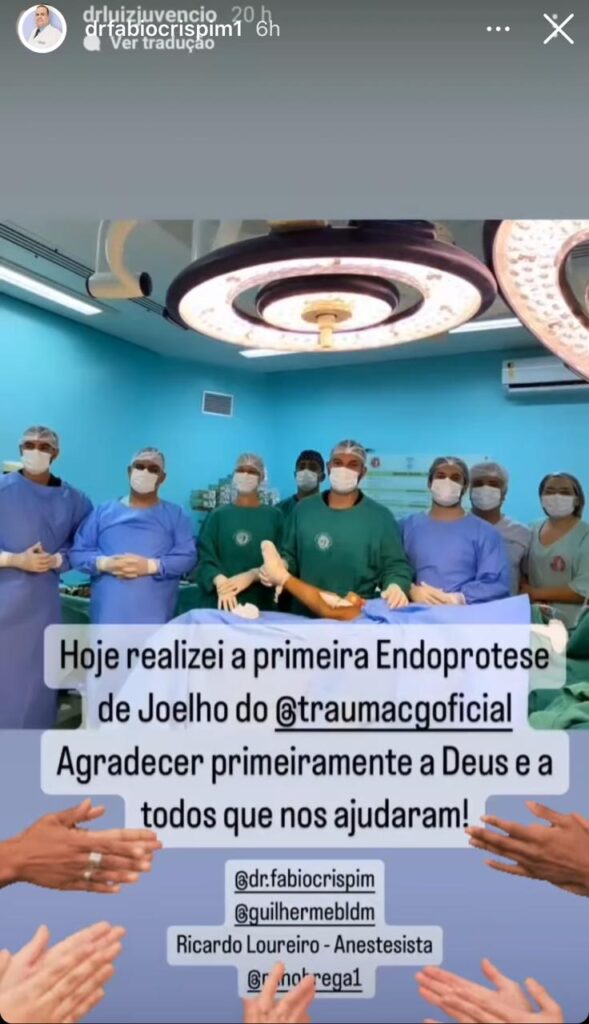

E, para a alegria de todos, na última sexta-feira, dia 15 de setembro de 2023, a Senhora Antonia Benedita da Cunha, natural de São Bento-PB, foi responsável por um feito inédito, uma vez que, foi A PRIMEIRA PACIENTE DA HISTÓRIA DO HOSPITAL DE TRAUMA DE CAMPINA GRANDE-PB A REALIZAR O PROCEDIMENTO CIRÚRGICO DE ENDOPROTESE DO JOELHO DIREITO.

Na oportunidade, o Dr. Flauber José, CEO do Escritório Flauber José Advocacia, advogado da paciente, comentou a decisão: “Estamos felizes em levar assistência médica a uma cidadã que tanto necessitava. Foi um longo processo, onde foi necessário demonstrar a urgência na realização do procedimento cirúrgico da paciente – que corria risco de perder sua perna – como também, foi necessário demonstrar a impossibilidade financeira para arcar com custos tão elevados na aquisição da prótese e seu procedimento cirúrgico. Por essa razão, a Justiça prevaleceu, o direito foi reconhecido, e o principal, a Sra. Antonia Benedita tendo sua saúde restaurada sem custo algum.”

Ademais, informamos que a são-bentense já está em fase de adaptação da prótese, sendo acompanhada por uma equipe de fisioterapeutas e médicos ortopedistas, e, nos próximos dias, receberá alta hospitalar e retornará a sua terra natal, São Bento-PB.